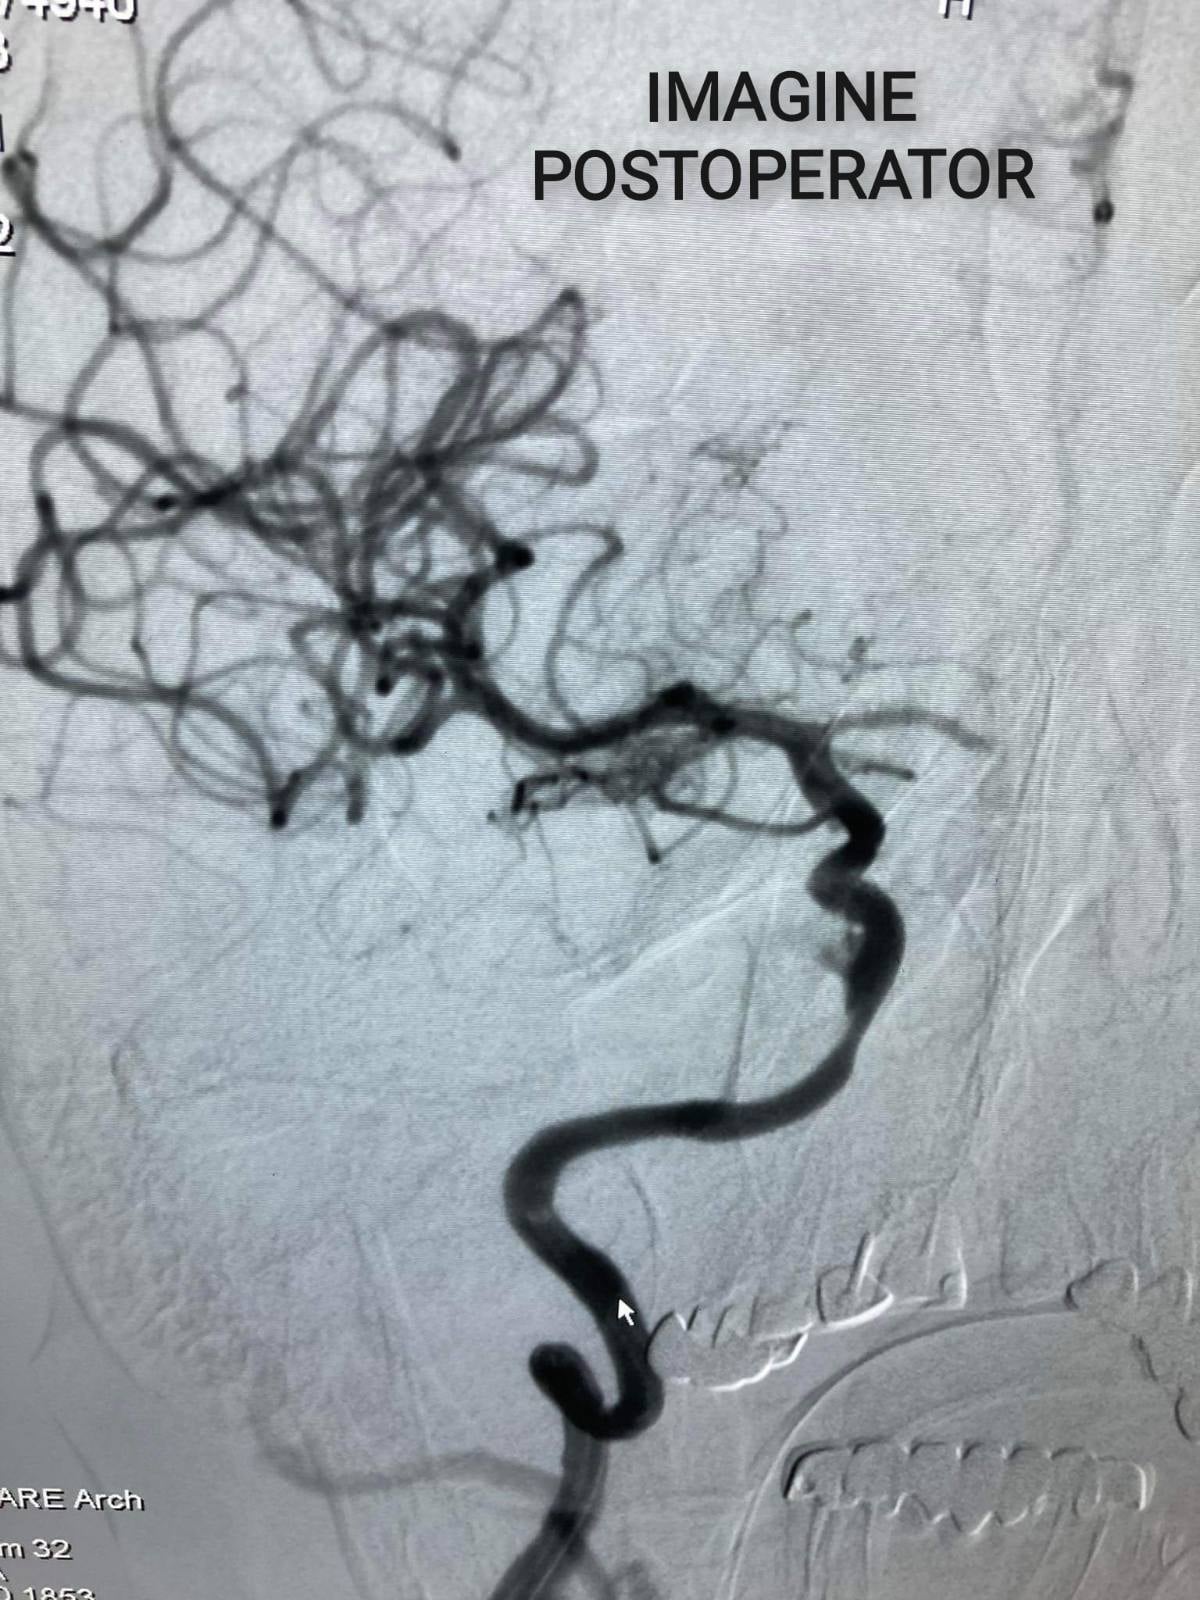

”Pacienta a fost operată în cadrul Cabinetului de cardiologie intervențională. Acesteia i s-a implantat dispozitivul de deviere de flux, prin excluderea anevrismului. Femeia a fost externată în stare satisfăcătoare a doua zi după intervenție. Menționez că, ictusul hemoragic provocat de anevrismele cerebrale complicate cu hemoragie este una din cauzele majore de dizabilitate și deces, iar metoda descrisă soluționează problema anevrismelor cerebrale minimal invaziv fără necesitatea unei intervenții majore pe creier”, a explicat chirurgul endovascular, Sorin Barat.